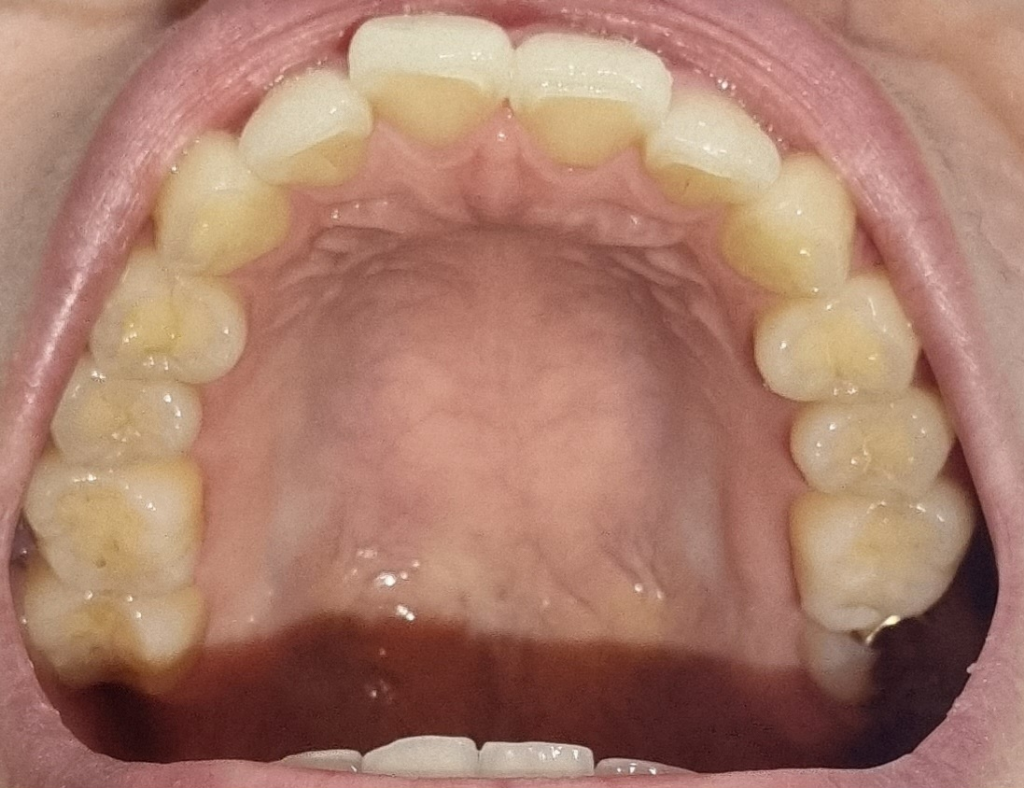

치아마모가 심한편인가요? 관리를 어떻게 해야할까요?

1. 치아 마모가 심각한 수준일까요?

• 1번 째 사진

사진상으로 보면 치아 마모상태가 심한거 같진 않습니다. 턱관절이 아프거나 그럴경우에는 스플린트나 보톡스 치료를 받으시면될것같습니다.

1. 사진상 치아 마모가 아주 심한 수준은 아니라고 판단됩니다.